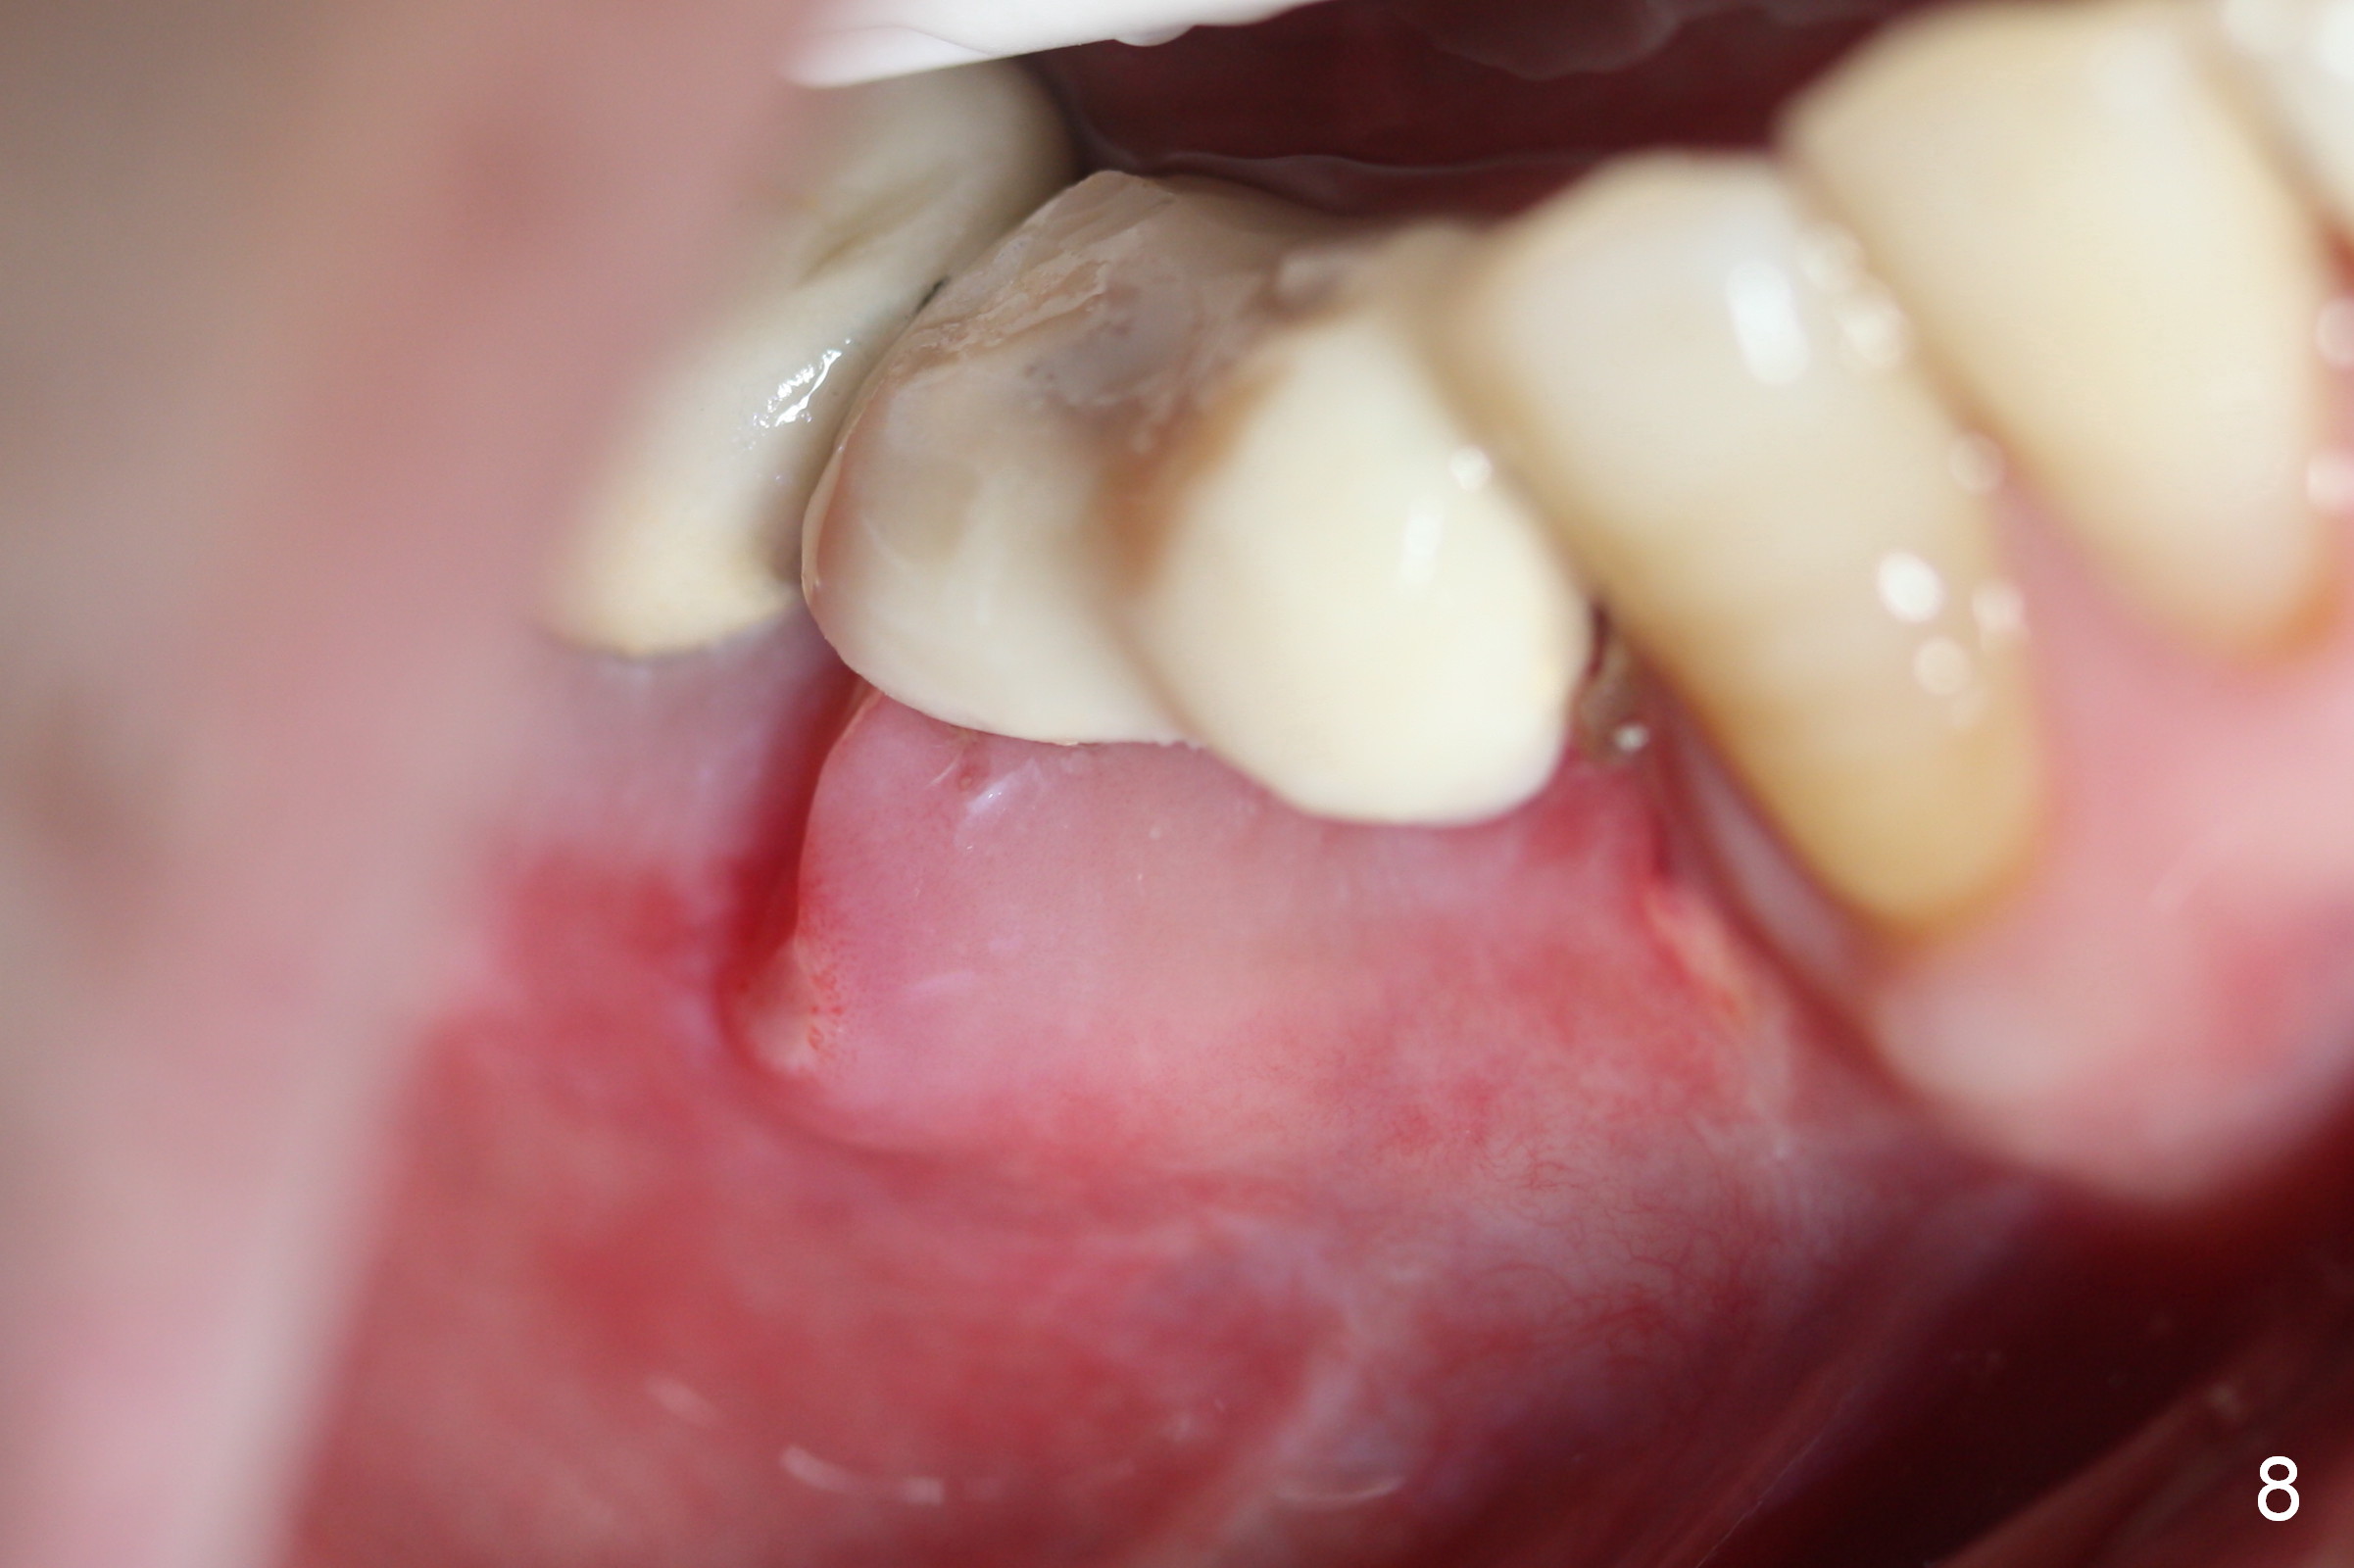

The perio dressing remains in place 1 week postop (Fig.7). After its removal, the wound is healing (Fig.8).